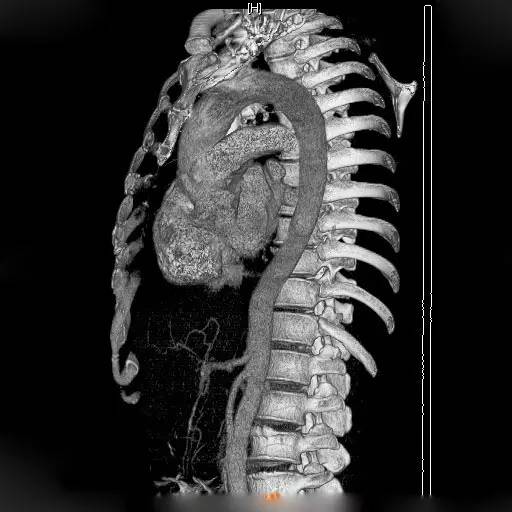

2.1 CT表现通常是主动脉壁呈新月或环形增厚,而主动脉真腔可发生变形或略变细,如图1所示,也可以正常。增强CT对IMH的显示通常优于平扫CT。